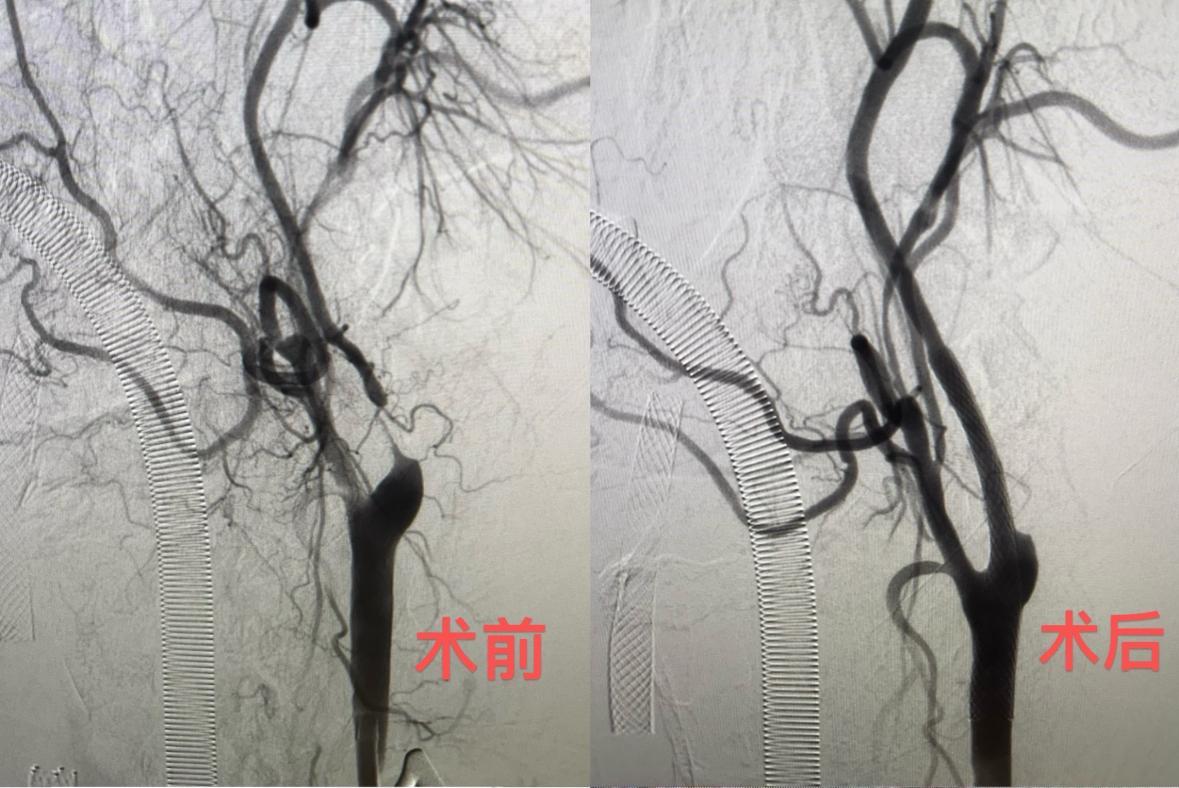

6月11日,该院神经外科陈光忠主任医师、秦琨副主任医师联合神经内科代成波主任团队,在神经电生理室、麻醉科和手术室等科室支持下,成功开展颈动脉狭窄治疗的全新术式:经颈动脉血运重建术(TCAR)。颈部开口仅2厘米,血流阻断15分钟,整个手术仅用时一小时便顺利完成。术后从影像结果可见,术前已经几乎断裂的血运通道,术后血运立即恢复。6月13日,术后2天的李大叔就已顺利出院。